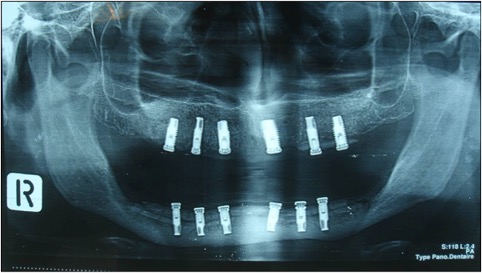

photo déroutement et greffe dans le même temps et résultat final avec implant.